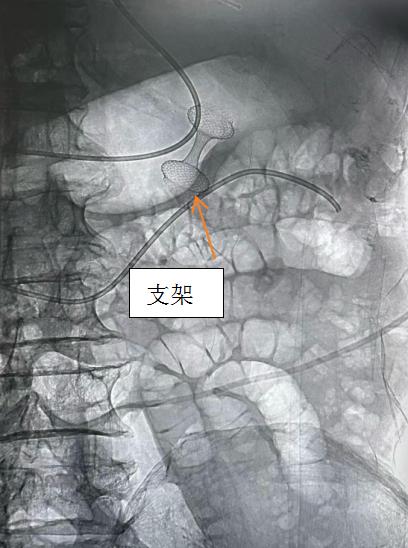

术中首先借助造影导管引导导丝穿过梗阻部位

在X线下定位至空肠

利用超声内镜扫查肠腔

设备经胃壁穿刺进入空肠并释放支架

连接胃与空肠的“人工桥梁”就此建立